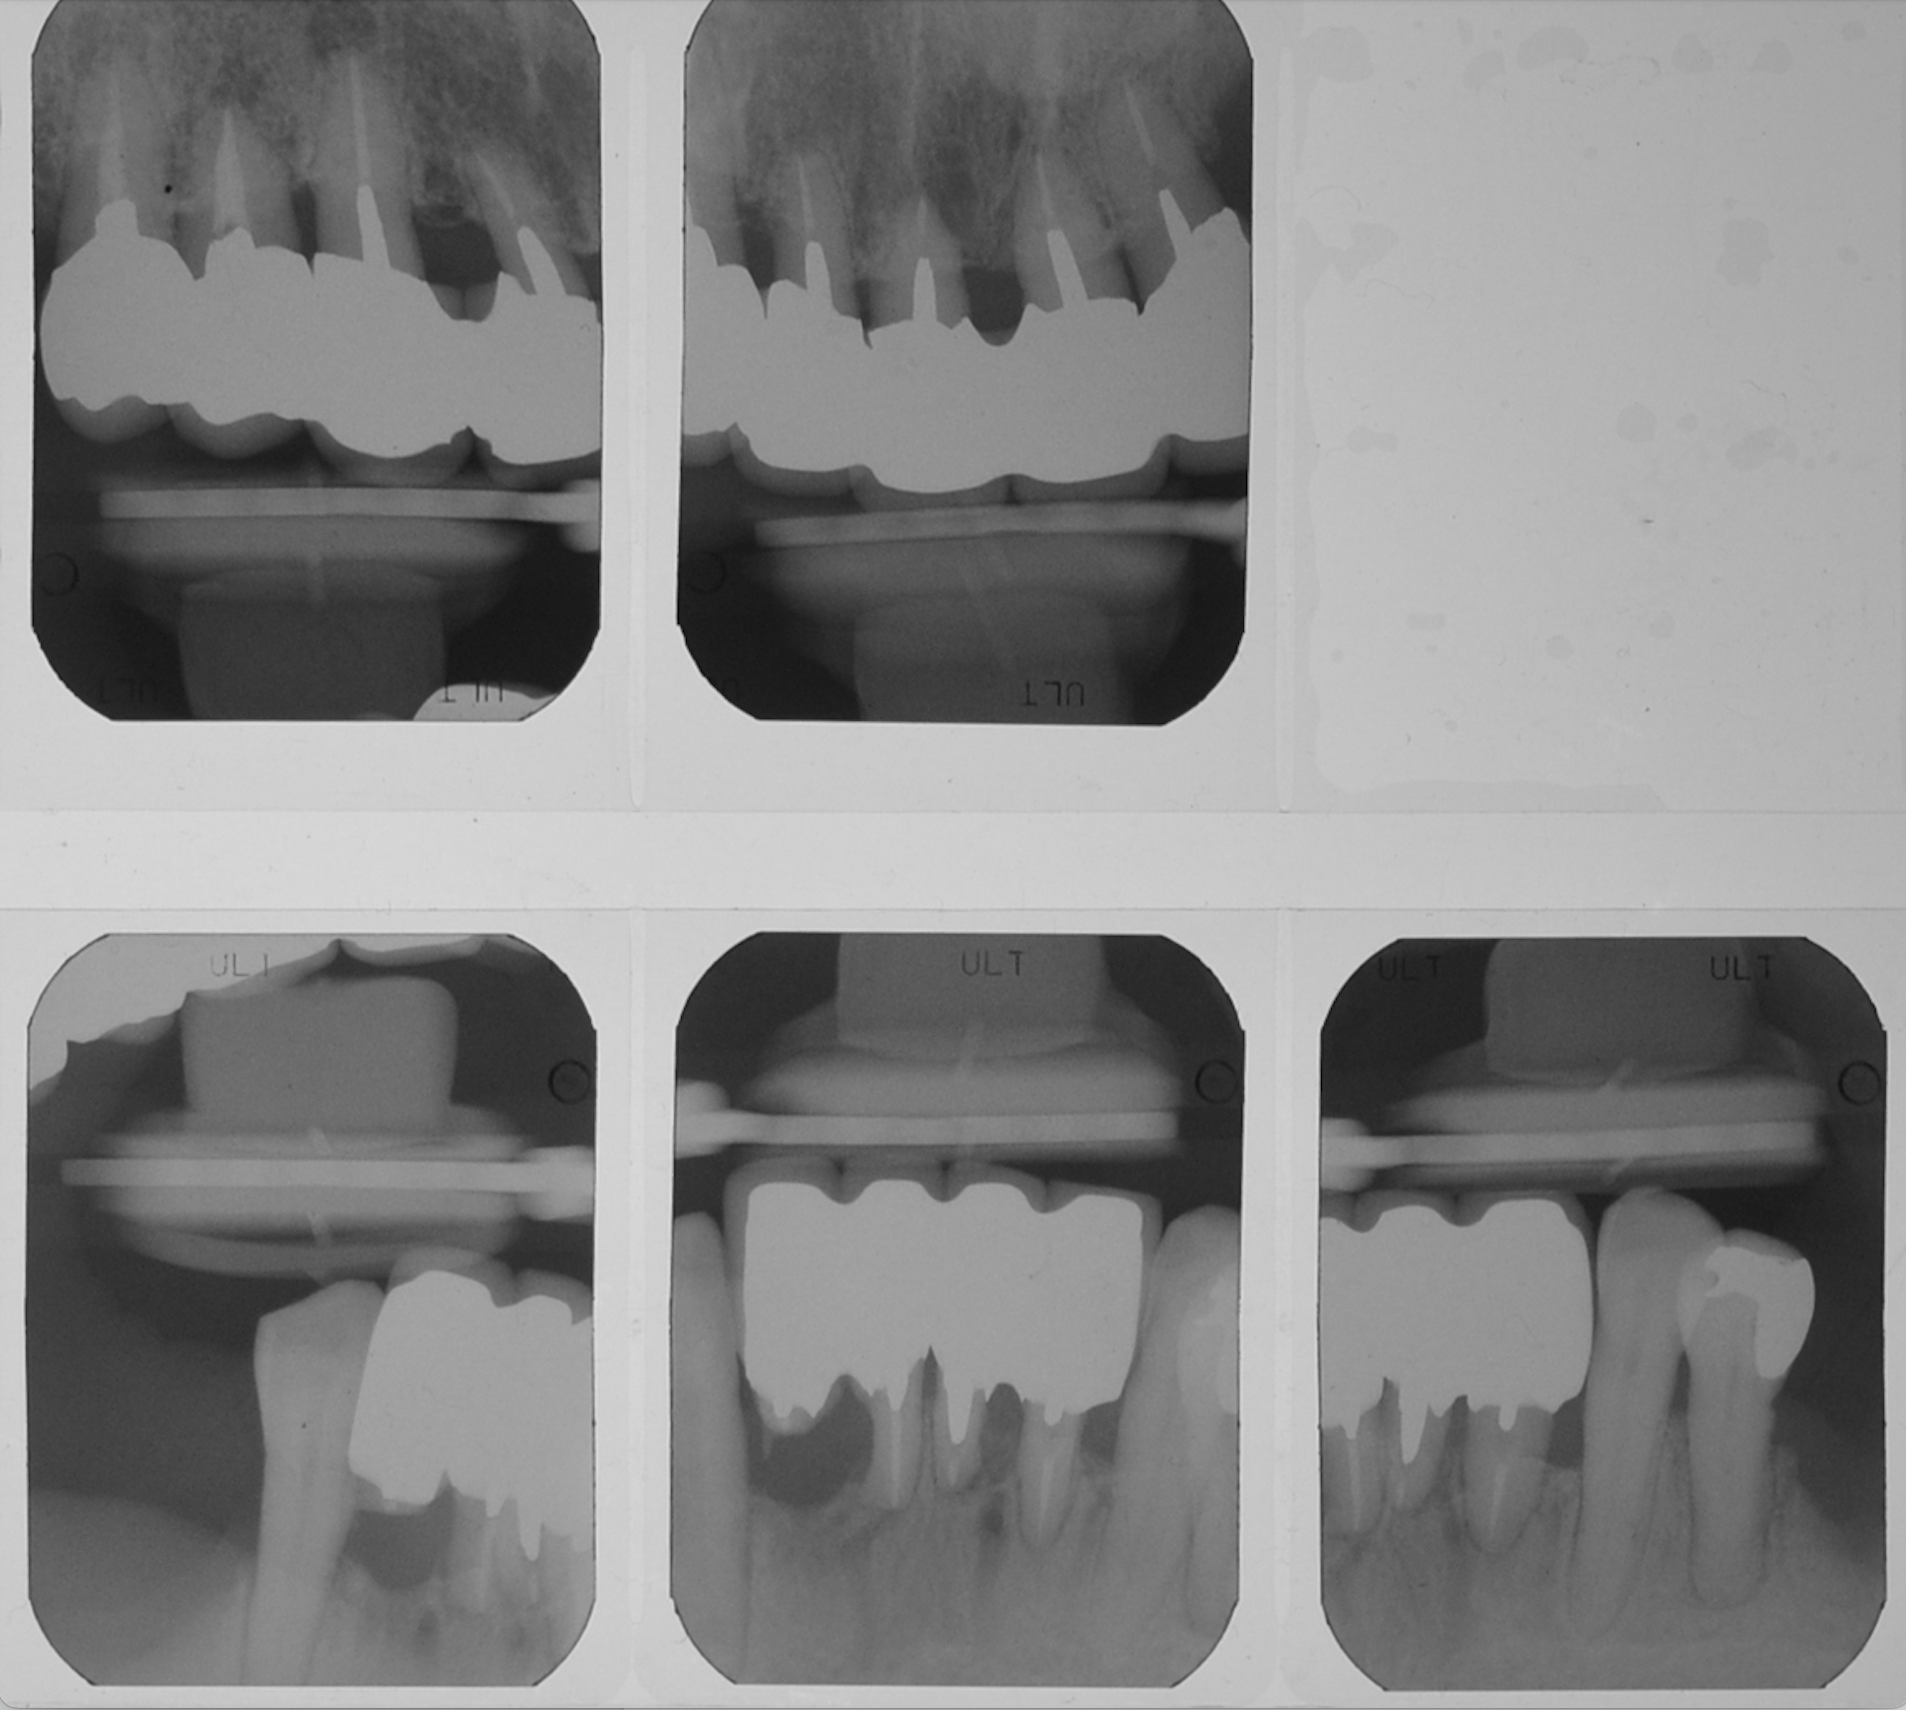

50代女性 部分義歯で対応した重度歯周病症例

娘さんがHPで安藤歯科を探していただいたそうです。義歯が入っているように見えない事が治療条件でした。

試適時の咬みわせチェックの写真です。装着時も咬合器にリマウントしてチェックします。

ステージIVグレードB 審美障害

FDI表記 23 25 26 35 37 42 44 45 47

1年

30

170万円